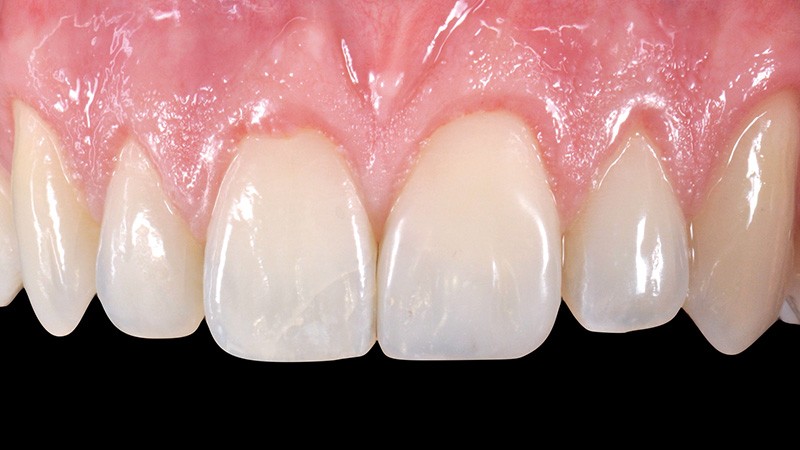

1. Situation initiale. Le composite a été refait trois fois durant

les deux dernières années, du fait de décollements répétés. La forme et le poli de surface sont à l’évidence perfectibles ; pourtant l’intégration du composite est correcte ! Cela prouve une nouvelle fois l’incroyable potentiel esthétique de ce matériau !